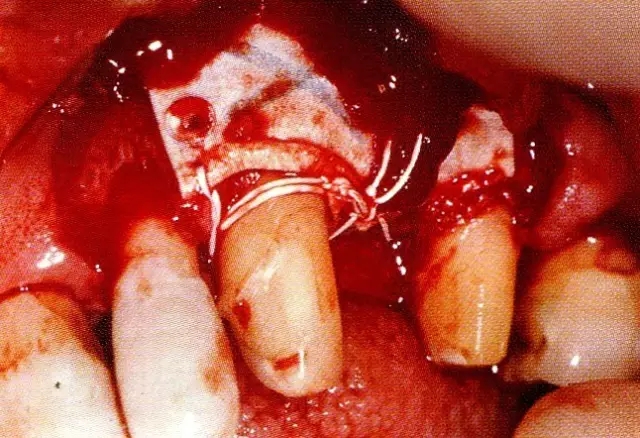

▲圖7-3  將posterior interproximal類型的非吸收性覆膜修整后進(jìn)行垂直懸吊縫合做固定。垂直懸吊縫合后,確定覆膜是否會動搖,再將齦瓣與之緊密縫合。